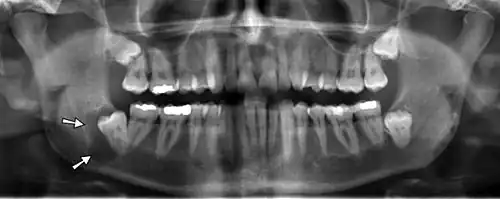

Panoramic radiographs have the capability to demonstrate a portion of the neck and display atheromas (calcifications in the carotid artery) which are an indication of both local and generalized (systemic) atherosclerosis. Atherosclerosis of the coronary arteries leading to myocardial infarction (heart attack), and atherosclerosis of the carotid artery leading to stroke are the number one and number three most common causes of death in the United States.[6]

There is interest to look at panoramic radiographs as a screening tool, however further data is needed with regards if it is able to make a meaningful difference in outcomes.[7]

Epidemiology: general public and high risk groups

Additional research projects have further determined the prevalence rate of these atheromas in the general population (3–5%)[8][9] and among high-risk groups (over 25% in: recent stroke victims,[10] individuals with obstructive sleep apnea syndrome,[11][12][13] postmenopausal women,[14] type 2 diabetics,[15][13][16] individuals with dilated cardiomyopathy,[17][13] and among individuals who have received radiotherapy directed at the neck,[18][19]). These findings have been corroborated by other several other researchers.[20][21][22][23][13]